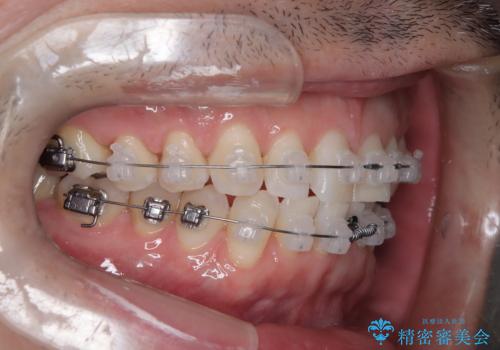

定期健診で歯並びを相談 セラミックブラケットでのワイヤー矯正例

- インシグニア デイモンクリア

- 治療計画

- 定期健診の際に、下顎前歯のガタつきが年々悪化しているとの相談を患者様より頂戴しました。下顎前歯の叢生(ガタつき)程度や患者様の希望もあり、非抜歯でも無理のない範囲と考えワイヤー矯正にて治療計画を立案しました。着色の少ないセラミックブラケットを使用しています。